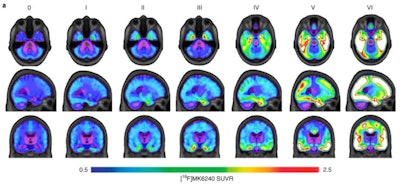

The Braak system stages patients with Alzheimer's disease according to tau aggregation in the transentorhinal cortex (stage I), entorhinal cortex and hippocampus (stage II), inferior temporal neocortex (stage III), association cortices (stages IV and V), and primary sensory cortices (stage VI).

First, the researchers assigned PET-based Braak stages to individual patients ranging from 0 (no detectable tau-PET abnormality) to VI (tau-PET abnormality extending to primary sensory areas) based on the accumulations of tau observed on PET scans. Next, they assessed the relationship between PET-based Braak stages and clinical dementia severity according to the Clinical Dementia Rating (CDR), an interview tool clinicians use to apply scores to cognitive function.

Average F-18 MK-6240 SUVRs across the whole brain for all participants, grouped according to PET-based Braak staging. Individuals at stage 0 did not have detectable tau abnormality in regions comprising any Braak stage. At stage I, tau abnormality is confined to the transentorhinal cortex. Braak stages V and VI are characterized by high magnitude of tau pathology, with stage VI extending to primary sensory cortices. Image courtesy of Nature Aging.